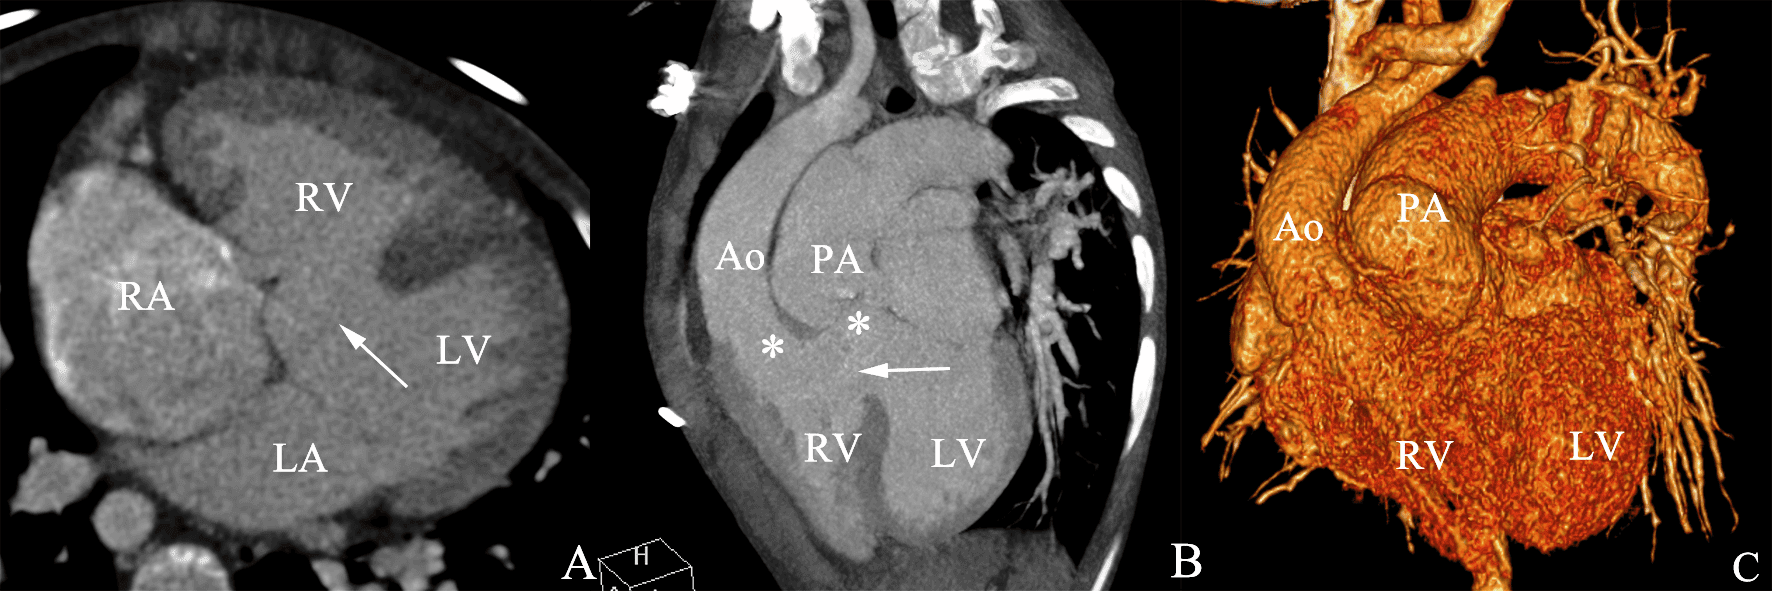

* Phân loại – Tư thế chụp thẳng sau trước (PA): chỉ thấy các bờ phía ngoài của tim – Tư thế chụp nghiêng: * Tư thế thẳng * Tư thế nghiêng – Thông liên thất (Ventricular septal defect – VSD) là một khiếm khuyết của vách liên thất, tức là vách ngăn giữa hai buồng tâm thất của tim. Vách liên thất là một cấu trúc phức tạp gồm: phần cơ, phần màng, phần phễu, phần buồng nhận. – Nguyên nhân: hiện chưa rõ, tuy nhiên ncó đề cập tới 1 số yếu tố như do di truyền hay gia đình: cha mẹ hay anh, chị em mắc bệnh tim bẩm sinh trong đó có bệnh TLT thì có nguy cơ mắc bệnh cao hơn. Tương tự ở – Sinh lý bệnh: – Phân loại: * Chẩn đoán X-Quang – Hội chứng Eisenmenger: trường hợp Shunt (T) => (P) lâu ngày, dẫn đến tăng áp động mạch phổi làm đảo ngược Shunt (P) => (T), kèm tím tái: * Cắt lớp vi tính: – Thông liên nhĩ (Atrial Septal Defect – ASD) là một dạng bệnh tim bẩm sinh làm cho máu chảy giữa hai buồng nhĩ trái và nhĩ phải. Bình thường nhĩ trái và nhĩ phải tách biệt nhau bởi một vách được gọi là vách liên nhĩ. Nếu vách này bị khiếm khuyết hoặc không có, máu giàu oxy có thể chảy trực tiếp từ bên trái của tim để trộn với máu kém oxy ở bên phải của tim và ngược lại. Điều này có thể dẫn đến máu động mạch cung cấp cho não, các cơ quan và các mô có nồng độ oxy thấp hơn bình thường. – Phân loại: * Chẩn đoán X-quang => Case lâm sàng 1: * Chẩn đoán CT: thuốc cản quang chảy từ nhĩ trái sang nhĩ phải. * Hội chứng Eisenmenger – Còn ống động mạch (Patent ductus arteriosis – PDA) tình trạng ống động mạch (ống Botal) nối giữa động mạch chủ và động mạch phổi trong thời kỳ bào thai không bị tắc lại sau sinh (thông thường ống này sẽ hoàn toàn tắc lại trong vòng 2 tháng sau sinh), mà vẫn tiếp tục tồn tại và hoạt động kéo dài. * Hình ảnh X-quang * Chẩn đoán CT => Case lâm sàng 1: => Case lâm sàng 2: => Case lâm sàng 3: => Case lâm sàng 4: => Case lâm sàng 5: – Tứ chứng Fallot (Tetralogy of Fallot – 4F) là bệnh tim bẩm sinh tím thường gặp nhất với tỉ lệ 10% trẻ bị tim bẩm sinh. – Tứ chứng Fallot là bệnh lý tiến triển nặng theo thời gian. Tùy theo mức độ hẹp đường thoát thất phải và kích thước thông liên thất, triệu chứng tím thường xuất hiện trong giai đoạn nhũ nhi hoặc trẻ nhỏ. Trong những trường hợp nặng, tím xuất hiện ngay từ những ngày đầu sơ sinh. * Hình ảnh X-quang => Case lâm sàng 1: => Case lâm sàng 2: – Hẹp eo động mạch chủ (Coarctation of aorta – COA) thường hẹp sau chỗ xuất phát động mạch dưới đòn trái. Hậu quả, dòng máu trước chỗ hẹp bị cản trở, khiến áp lực buồng tim gia tăng, dẫn tới phì đại thất trái và suy tim. – Hình ảnh X-quang: => Case lâm sàng 1: => Case lâm sàng 2: => Case lâm sàng 3: => Case lâm sàng 4: => Case lâm sàng 5: * Giả hẹp eo động mạch chủ => Case lâm sàng 1: => Case lâm sàng 2: => Case lâm sàng 3: => Case lâm sàng 4: * Chẩn đoán CT => Case lâm sàng 1: => Case lâm sàng 2: => Case lâm sàng 3:II. Giải phẫu

– Hình ảnh đảo ngược shunt có thể được xác định nếu nhìn thấy thuốc cản quang chảy từ bên phải của trái tim sang bên trái.3. Còn ống động mạch